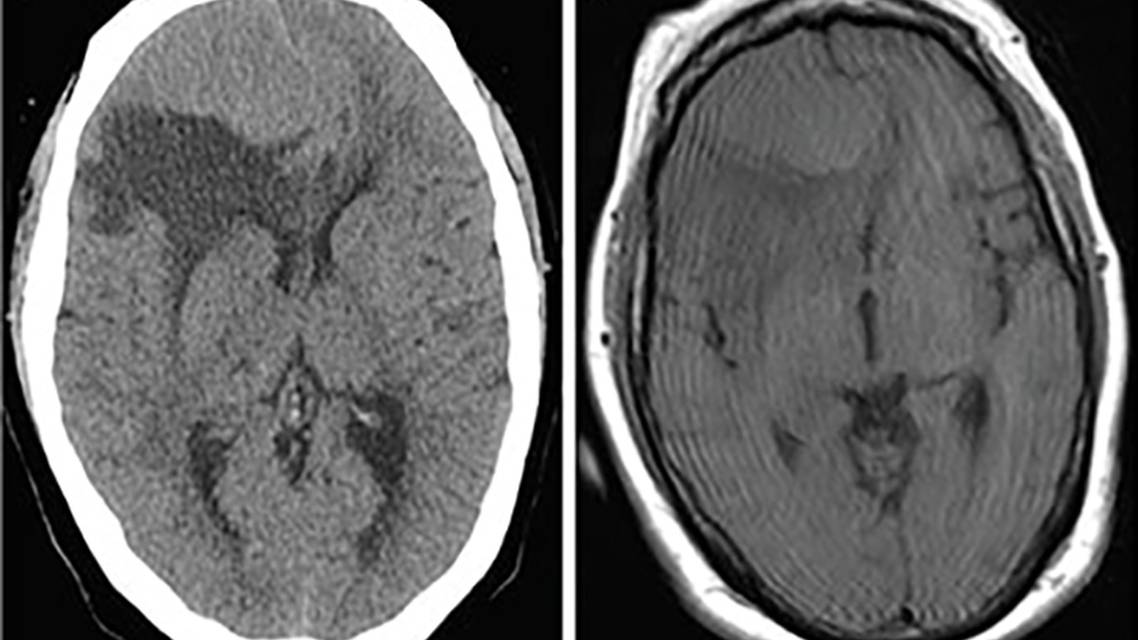

CT. The most common initial radiographic evaluation for suspected brain tumors is CT, despite the need for subsequent MRI because CT is useful for identifying acute hematoma, mass effect, herniation, and hydrocephalus. Additionally, CT can identify tumor calcifications to suggest either, craniopharyngioma (suprasellar), oligodendroglioma (intra-axial) or meningioma (extra-axial) (Figure 1A).11

A homogenously enhancing extra-axial mass suggests meningioma, but the differential diagnosis includes hemangiopericytoma, dural-based metastasis, and lymphoma (Figure 1). A solitaryT2/FLAIR hyperintense intra-axial lesion that does not enhance with contrast suggests low-grade glioma (Figure 2). A solitary heterogeneously enhancing intra-axial lesion suggests high-grade glioma or solitary metastasis (Figure 3). Multiple heterogeneously enhancing intra-axial lesions suggests a metastatic disease or abscesses (Figure 4).